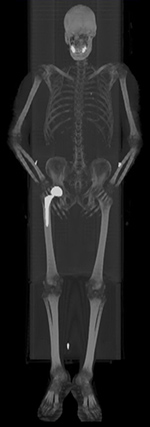

Normal whole body pediatric and adult bone scintigraphy with technetium 99m methylene diphosphonate (MDP) display different features (figure 1). In the pediatric population there is intense radiotracer uptake in the growing physes of long bones. Normal adult whole body planar bone scans with Tc-99m MDP demonstrates normal expected uptake in the bilateral sacroiliac joints, iliac crest, acromioclavicular joints, sternoclavicular joints, and nasal region. Normal radiotracer activity is excreted into the kidneys and urinary bladder.

| Normal pediatric whole body Technetium 99m-methylene diphosphonate (Tc-99m MDP) bone scan displays intense expected radiotracer uptake in the physes of long bones. |

Normal adult whole body bone scan Tc-99m MDP demonstrates normal expected uptake in the bilateral sacroiliac joints, iliac crest, acromioclavicular joints, sternoclavicular joints and nasal region. Normal radiotracer activity is excreted into the kidneys and urinary bladder. |